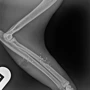

Cats Protection Moray was contacted on 8 May after a feral cat appeared at a haulage yard, where workers regularly left food and provided shelter for him. They were shocked to see that the cat was limping after being shot in the leg.

A worker at the yard notified the charity’s Trap, Neuter, and Release Volunteer, Kat Hibbert-Jordan, who immediately went to trap the cat and took him to the Cairngorm Vets. The injuries were found to be consistent with a gunshot wound.